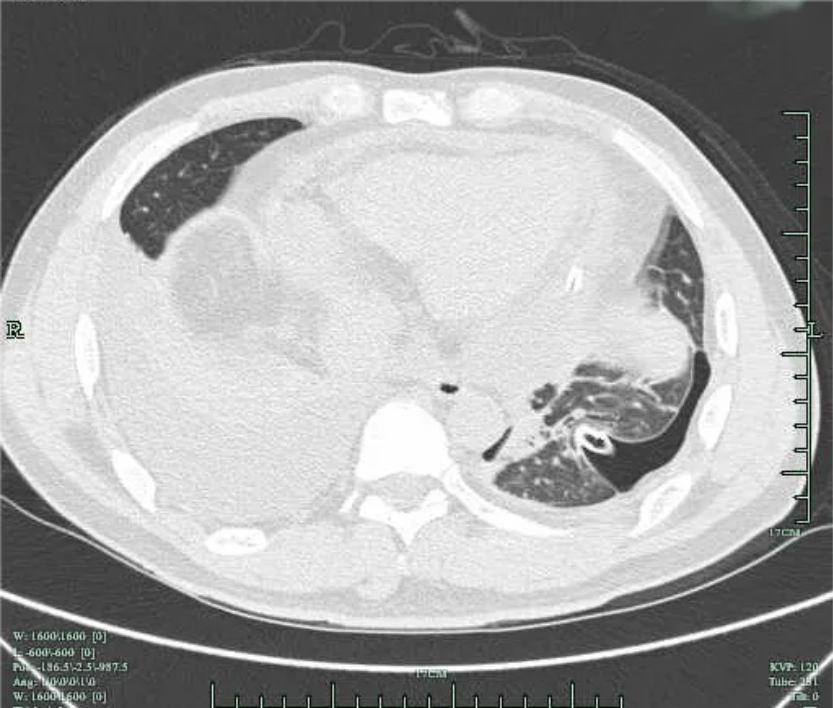

患者3周(2022年10月10日)前出现左前胸及侧胸疼痛,呈阵发性隐痛,能忍受,疼痛无放射性,否认疼痛时黑曚、汗出、否认畏寒发热等,社区医院用药(具体药名不详)后好转;1周前(10月23日)左侧胸部出现压榨痛,疼痛呈持续性不能缓解,伴胸闷气急,至县医院就诊:血常规:白细胞 11*10^9/L(3.5-9.5*10^9/L),血红蛋白及血小板正常;超敏C反应蛋白:67.95mg/L(0.00-3.30mg/L),心电图示:V2-V5导联ST段凹面向上稍抬高(图1);10月24日肺部CT示(图2):左肺散在炎症,左侧胸腔少量积液伴邻近肺组织膨胀不全,两肺散在纤维灶,心包积液,升主动脉增宽;10月24日心超示:三尖瓣反流,左室舒张功能减低,心包积液(心尖部心包分离约0.5cm),心动过速,EF:57%。

图2 肺部CT 肺窗提示 右侧胸腔积液,左侧胸腔积液引流后改变